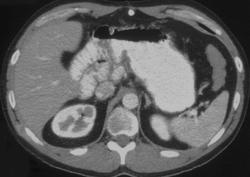

Cystic Fibrosis With Dilated Bowel